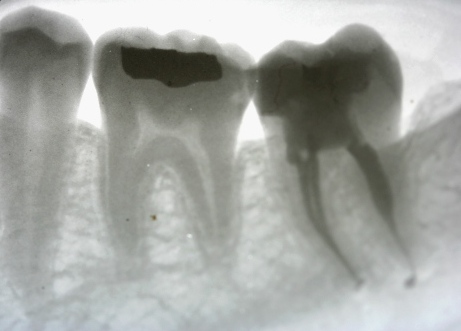

Root Canal by Mark Dennis,DDS

DENTIST

Mark Dennis DDS dental office